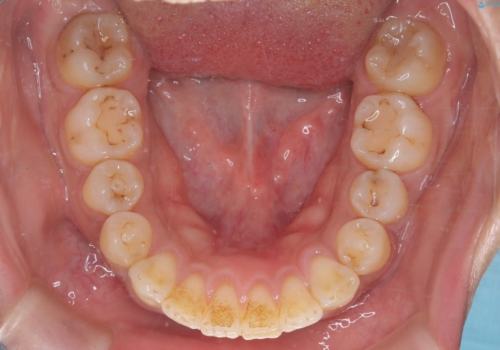

- 主訴:学生時代に矯正治療したが、後戻りしてしまった。上下前がのガタつきを治したい。

食品関係に努めており、頻繁に物を口にするためマウスピース矯正は装着時間を守ることが難しいことから非抜歯のワイヤー装置にて治療することとなりました。

ワイヤー矯正(審美装置)非抜歯 治療期間:1年8か月

一日に物を口にする回数が多い方はマウスピース矯正における推奨装着時間を守ることや、その都度歯磨きをすることが難しいため、ワイヤー矯正での治療となりました。

途中、大臼歯の遠心移動のためリンガルアーチを使用しています。